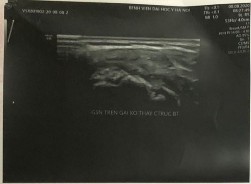

Hình phụ lục 2D: Hình ảnh liền gân độ 1 trên Siêu Âm và độ 2 trên CHT khi khâu phục hồi tổn thương ở tháng thứ 7 sau mổ

(Nguồn: BN nghiên cứu)